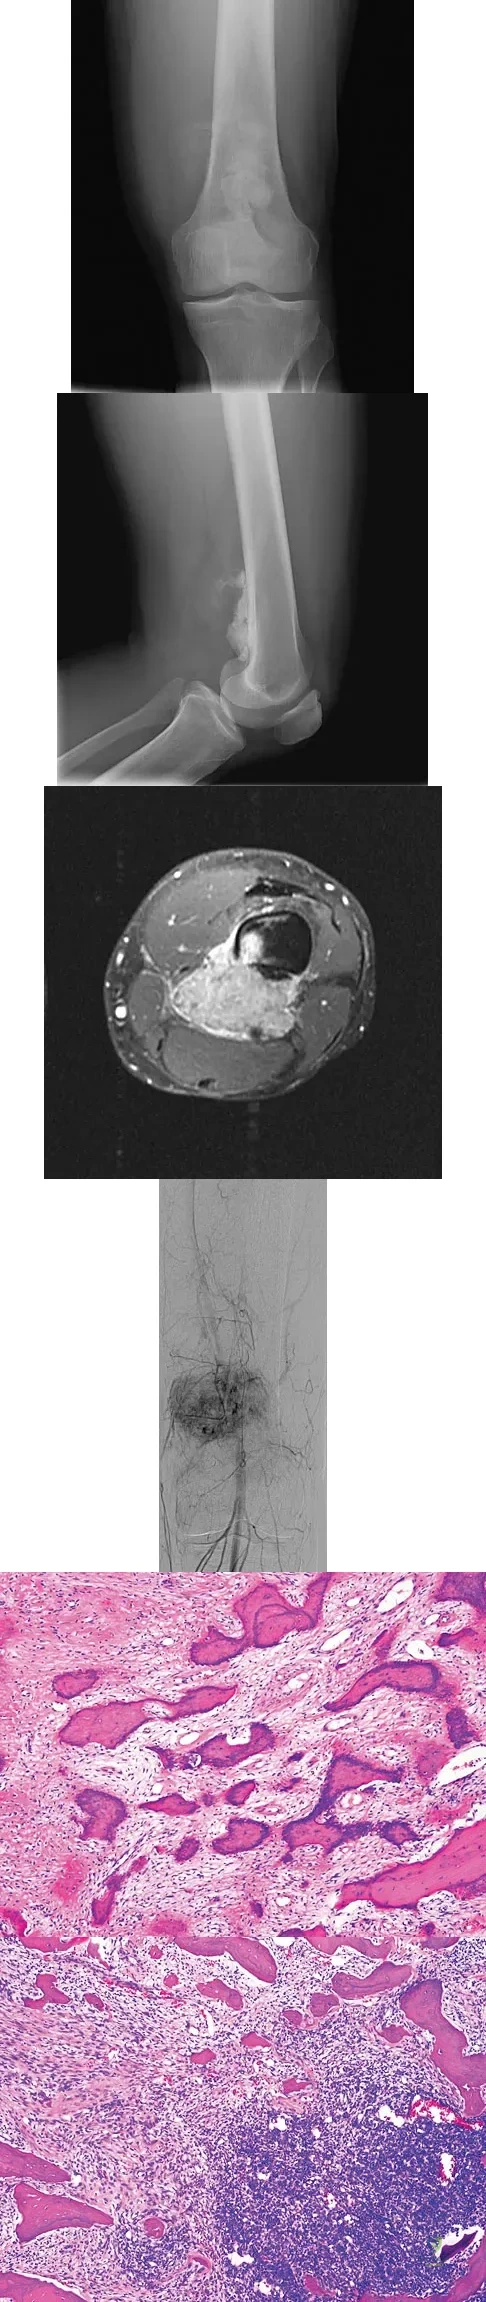

Question 77High Yield

An otherwise healthy 33-year-old man who works in construction reports a 3-month history of knee pain. Radiographs are shown in Figures 9a and 9b. An axial T1-weighted MRI scan with contrast, an angiogram, and histologies are shown in Figures 9c through 9f. What is the most likely diagnosis?

Explanation